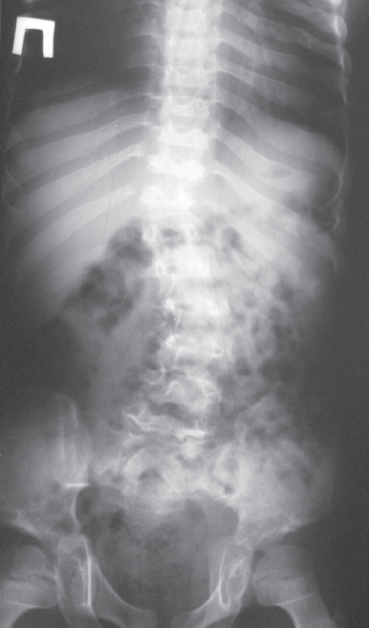

The review is devoted to the clinical, biochemical, and molecular genetic characteristics of autosomal recessive mucopolysaccharidoses (MPS) types IV, VI, and VII. MPS IV type, or Morquio’s syndrome, is represented by 2 types – A and B. The cause of the most frequent MPS IVA is hereditary deficiency of galactose-6-sulfatase, due to the presence of inactivating mutations in the GALNS gene. The pathogenetic basis of the disease is associated with excessive accumulation in lysosomes, mainly of cartilage tissue of keratan sulfate and chondroitin-6-sulfate. Main clinical manifestations of MPS IVA are dwarfism and progressive deformity of the spine, sternum, and knees. The milder MPS IVB is due to hereditary β-galactosidase deficiency and is an allelic variant of GM1 gangliosidosis. The cause of MPS VI, or Maroto–Lamy syndrome, and MPS VII, or Sly syndrome, is hereditary deficiency of arylsulfatase B and β-glucuronidase, respectively. The pathogenesis of these diseases is due to the excessive accumulation of dermatan sulfate and, in the second case, additionally, heparan sulfate. Patients with type VI and VII MPS have a Hurler-like phenotype, but in the first case, intellectual deficiency are usually absent, while in Sly syndrome, moderate mental retardation is observed. The possibility of neonatal screening and early diagnosis of these MPS in order to increase the effectiveness of their prevention and treatment is discussed. The importance of experimental models for studying the molecular basis of the pathogenesis of these severe hereditary diseases and the development of various therapeutic approaches, such as bone marrow transplantation, enzyme replacement therapy and substrate-reducing therapy, is emphasized. Descriptions of clinical cases of MPS IVA and VI types are presented.